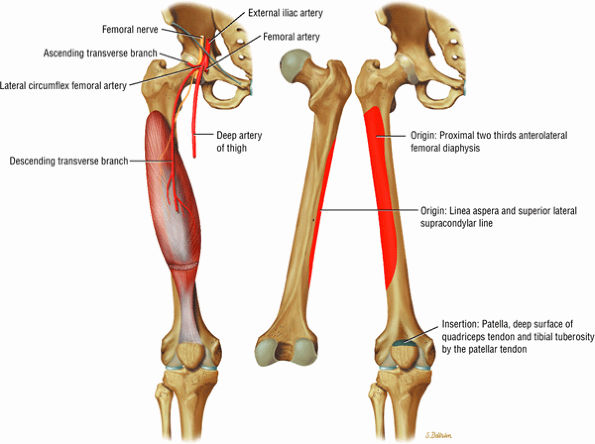

The anterior muscles of the thigh, including the sartorius (Fig. 3.5), the rectus femoris (Fig. 3.6), the vastus lateralis (Fig. 3.7), the vastus medialis (Fig. 3.8), and the vastus intermedius (Fig. 3.9). The vastus lateralis, vastus medialis, vastus intermedius, and rectus femoris are the quadriceps muscles.

FIGURE 3.9 ● VASTUS INTERMEDIUS The vastus intermedius extends the leg and covers the articularis genu. Quadriceps (vastus lateralis, vastus medialis, vastus intermedius, and rectus femoris) injuries, including strains and tendon ruptures, result from eccentric muscle contractions. The articularis genu muscle represents a few separate muscle fibers deep to the vastus intermedius and is responsible for contracting the knee joint capsule superiorly in extension.